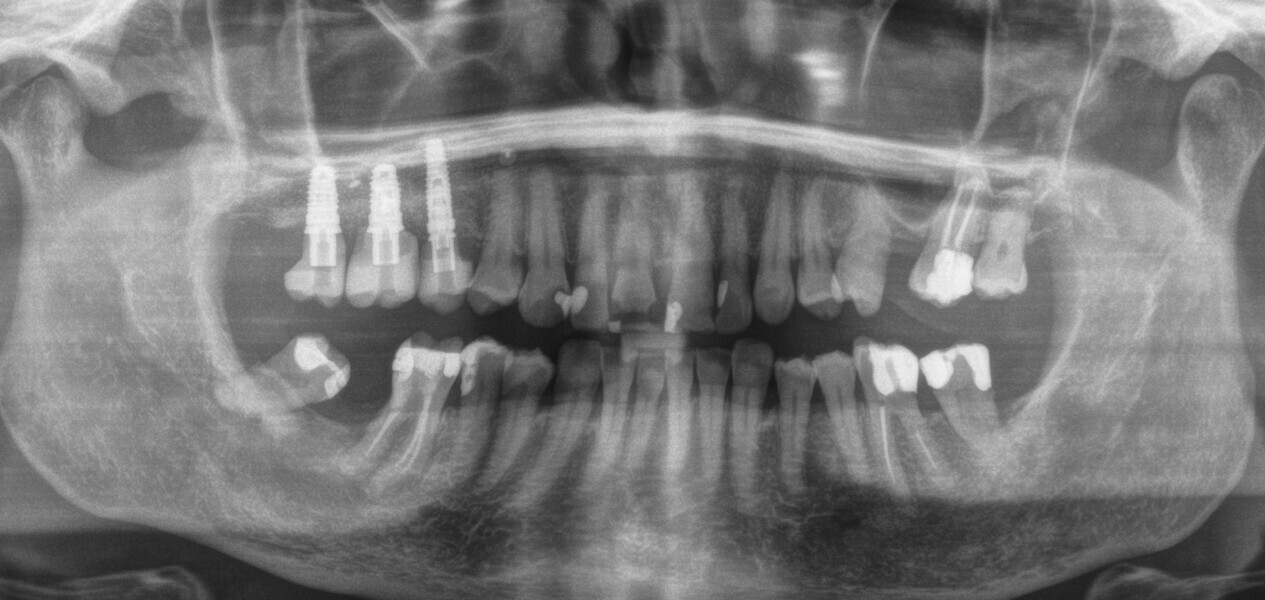

A 62-year-old female patient (ASA Class I), a non-smoker and with normal glucose levels, with previously treated periodontal disease presented for implant and prosthetic rehabilitation of the upper jaw (Fig. 1). Radiographic analysis, performed through a dental panoramic tomogram and CBCT scan, revealed the presence of a vertical bone defect in the right posterior sextant, due to the complete loss of the alveolar process (Figs. 2; 3a & b). The clinical examination showed the severity of the bone defect, which had resulted in an obvious volume deficiency in both the horizontal and vertical dimensions (Figs. 4 & 5).